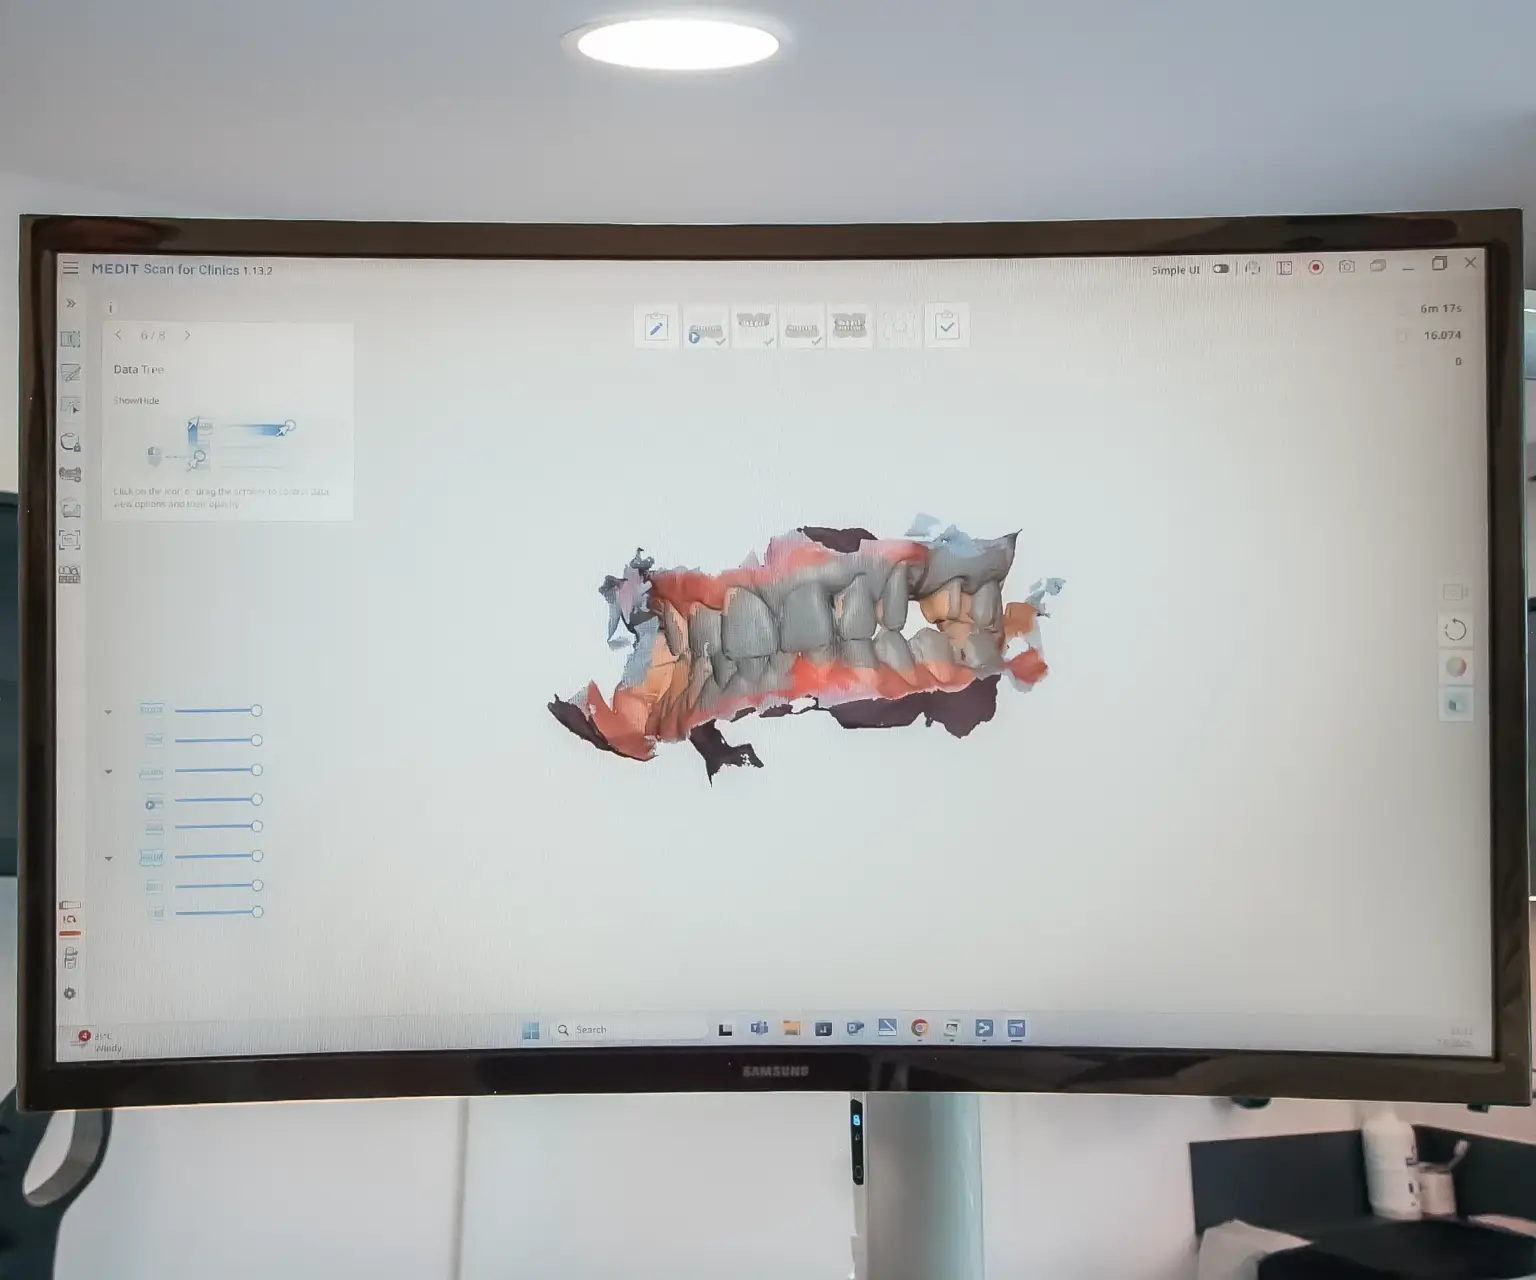

Intraoralni skener

Zaboravite na neugodno uzimanje otisaka pomoću klasičnih masa – intraoralni skener donosi revoluciju u dentalnoj dijagnostici. Umjesto fizičkih otisaka, koristi se digitalno skeniranje usne šupljine koje je brzo, precizno i maksimalno ugodno za pacijenta.

Ova metoda je posebno pogodna za osobe s osjetljivim refleksom na povraćanje jer ne zahtijeva kontakt s nepcem ni dubljim dijelovima usne šupljine. Skener omogućuje visoko precizne 3D prikaze zuba i zubnog luka, što značajno olakšava planiranje protetskih radova, ortodontske terapije i drugih zahvata.

Intraoralni skener doprinosi bržem postupku, smanjuje mogućnost pogrešaka i pruža bolje iskustvo za pacijenta.